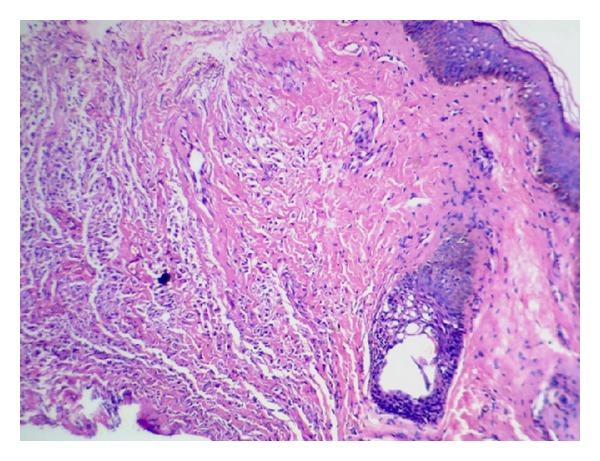

Solitary mastocytoma of the skin is a rare tumor. Its occurrence in the vulva is extremely rare with only few case reports in the literature. We report a solitary mastocytoma of the vulva in a 10-year-old girl. Her systemic examination was unremarkable. The clinical and histopathological features were consistent with the diagnosis of solitary mastocytoma of the vulva. The follow-up after surgical excision was uneventful. The purpose of this communication is (i) to report a case of solitary mastocytoma occurring in an unusual site, the vulva and to show that (ii) in this case age at presentation is 10 years with infancy as common age of presentation of solitary mastocytoma, and to show that (iii) in appropriate setting this should be included in the differential diagnosis of vulval swelling.

皮肤孤立性肥大细胞瘤是一种罕见的肿瘤。其发生于外阴极为罕见,文献中仅有少数病例报告。我们报告一例10岁女孩的外阴孤立性肥大细胞瘤。她的全身检查未见异常。临床和组织病理学特征与外阴孤立性肥大细胞瘤的诊断相符。手术切除后的随访过程顺利。本病例报告的目的是:(i)报告一例发生于不寻常部位(外阴)的孤立性肥大细胞瘤病例;(ii)表明该病例的发病年龄为10岁,而婴儿期是孤立性肥大细胞瘤的常见发病年龄;(iii)表明在适当情况下,应将其纳入外阴肿胀的鉴别诊断中。